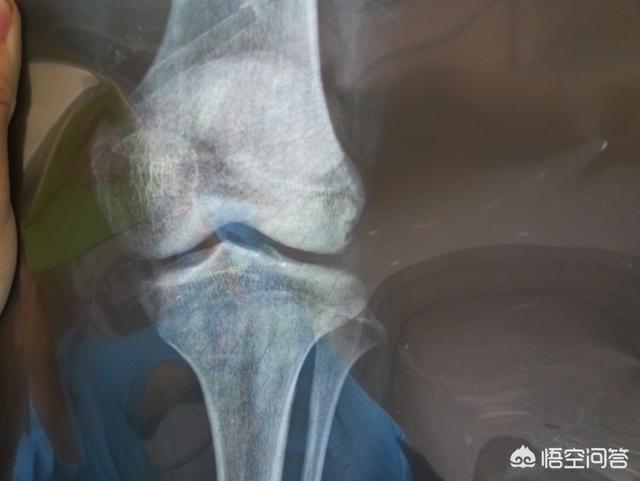

医学的には、月経後、骨端が閉じていない限り、まだ身長が伸びる余地はあります。本当に身長が伸びるかどうかを知りたいのであれば、病院に行って超音波検査で骨年齢を調べてもらうのが一番です。骨年齢が年齢を上回っていなければ、身長が伸びる可能性はあります。

したがって、女の子は1年間月経されている場合は、正常によると、すでに遅い開発である、あなたは骨年齢をチェックするために子供を取ることができ、子供の骨端が閉じているかどうかを知る、それが閉じている場合は、半年が成長しなかった、それは背の高い成長を停止することを意味します。